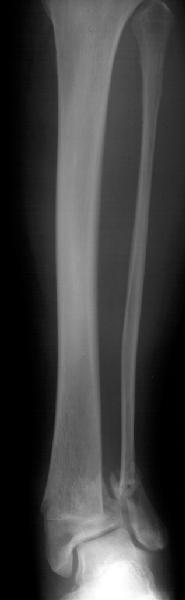

Subject: Tibia Fx - Comminuted Supramalleolar - Open

Middle aged adult was injured while travelling in a train(accidentally put his leg out). Presented with injury to left lower leg. Lacerated wound over the fibular fracture. Also another wound over the foot anterolaterally. No deficits.

On day one wound debridement followed by calcaneal traction done. Needs further stabilisation and a small split graft laterally. At present the fragments are putting pressure on the anterior skin. Will be happy to get your opinion on possible methods of stabilisation.

Day 1

Traction